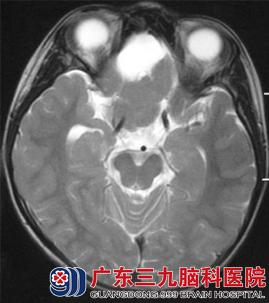

CT表现(图1、2):前颅窝底可见一等密度(与脑实质密度相同)占位性病变,其前方可见囊性的低密度影,与脑脊液密度相似,相邻脑组织受推压,未见明显水肿密度影。MR表现(图3-6):病变呈等T1等T2信号,边界清晰;其前方可见长T1长T2信号影,增强后,病变未见强化。弥散加权成像(DWI):未见病变弥散受限,前方囊性部分呈低信号。考虑为前颅窝脑外占位性病变。

图4 T2WI轴位:病变呈等信号,其前方囊性部分呈高信号